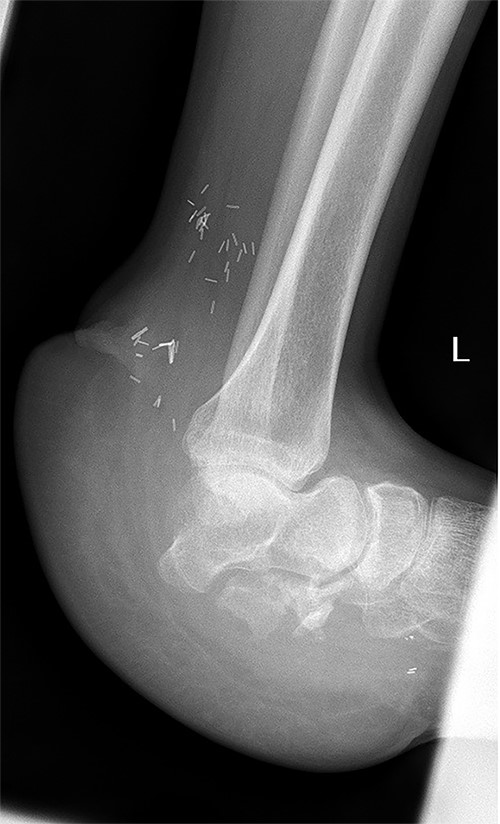

The treatment of calcaneus fractures is a challenge because of inadequate vascularity of this region [5]. Open fractures of the calcaneus are rare, ranging between 0.8 and 10% of all calcaneal fractures, and there are only a few reports described so far [6–9]. Further complicating their management, open fractures of the calcaneus carry higher incidence rates of infection, which range from 37 to 60% [7–9]. Treatments of complex calcaneal fracture include muscle and myocutaneous flaps, partial calcanectomy, total calcanectomy and below-the-knee amputation [8]. Traditionally, amputation has been the treatment of choice for extensive involvement of the calcaneus [5,10]. Recently, muscle flaps with skin grafts have become the preferred choice when filling wounds that have osteomyelitis at the base [8]. The aim is to facilitate the initial phase (heel strike) of the gait cycle, and rearrange the distribution of pressure over foot [9]. Due to the rare occurrence of open calcaneal fractures, there is a paucity of published data on soft tissue reconstruction alone for these injuries in the orthopedic and reconstructive surgical community. Our patient had a large calcaneal bone and soft tissue defect; thus, we selected a tensor fascia lata free flap alone for reconstruction of the defect. Advantages of this flap include reliable blood supply, bulky subcutaneous tissue and fascia, which can be used to cover large defects [9]. For this flap, the vascular pedicle anatomy is more constant [11]. Other advantage of this flap is its hidden and less visible site; minimizing aesthetic concerns [8]. In our patient, weight bearing was initiated 1 month after surgery. At 18-month postoperatively, the patient had a near normal painless gait, normal plantar sensation and no difficulty climbing or descending stairs with stable talonavicular joint (Fig. 4). The patient recovered near full range of motion and complete independent mobility.

X-ray of the left foot 18 months post flap coverage showing a stable talonavicular joint.